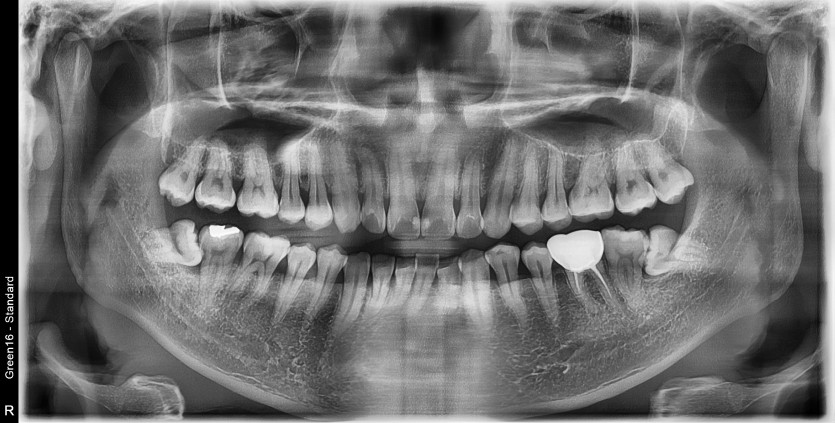

#18,28,38,48 사랑니 발치

구강 외과 전문의가 당일 발치했습니다.